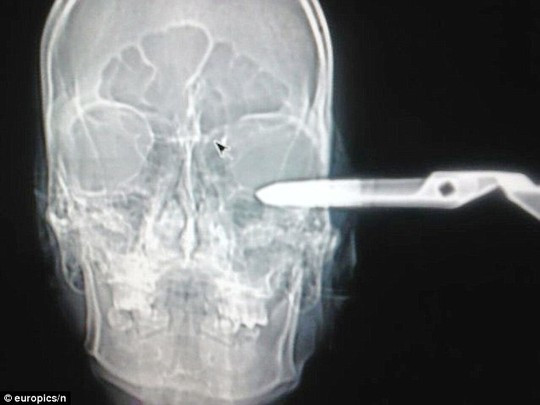

Hình chụp X-quang của Jonas Acevedo Monroy.

“Ban đầu, chúng tôi nghĩ đó chỉ là một trò đùa nhưng sau đó anh ấy ngất xỉu, chúng tôi vội vã đưa anh vào phòng cấp cứu. Bệnh nhân bị đâm vào phía trên bên trái hộp sọ, cây kéo đã xuyên qua đỉnh thùy não - nơi chịu trách nhiệm cho cảm giác, tri giác, nhận thức xử lý thông tin dựa trên hình ảnh trực quan. Anh ấy thật may mắn khi vẫn còn sống”, phát ngôn viên cho biết thêm.